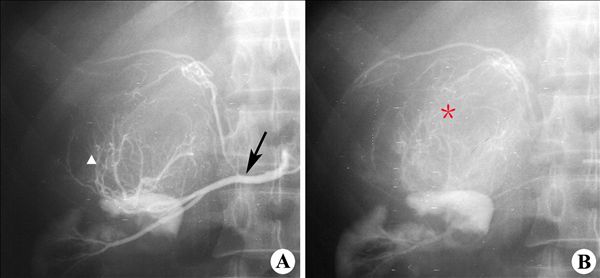

影像表现:肾上腺动脉造影(A)示肾上腺下动脉(↑)与肾上极一供血分支共干,肾上腺下动脉明显增粗,肾上腺区可见粗细不均肿瘤新生血管(▲),迂曲呈球形;实质期(B)可见不均匀肿瘤染色,勾画出肿块轮廓(*),肾上极显影清楚,未受侵蚀。

影像诊断:肾上腺嗜铬细胞瘤1.